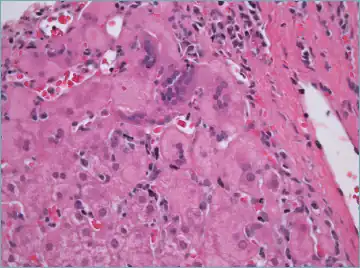

Histological features supportive of a diagnosis of autoimmune hepatitis include:[10]

- A mixed inflammatory infiltrate centered on the portal tract

- The inflammatory infiltrate may breach the interface between the portal tract and liver parenchyma: so-called interface hepatitis

- The most numerous cell in the infiltrate is the CD4-positive T cell.

- Plasma cells may be present within the infiltrate. These are predominantly IgG-secreting.

- Eosinophils may be present within the infiltrate.

- Emperipolesis, where there is penetration of one cell through another, within the inflammatory infiltrate

- Varying degrees of necrosis of periportal hepatocytes.

- In more severe cases, necrosis may become confluent with necrotic bridges forming between central veins.

- Hepatocyte apoptosis manifest as acidophils or apoptotic bodies.

- Rosettes of regenerating hepatocytes.

- Any degree of fibrosis from none to advanced cirrhosis

- Biliary inflammation without destruction of biliary epithelial cells in a minority of cases.